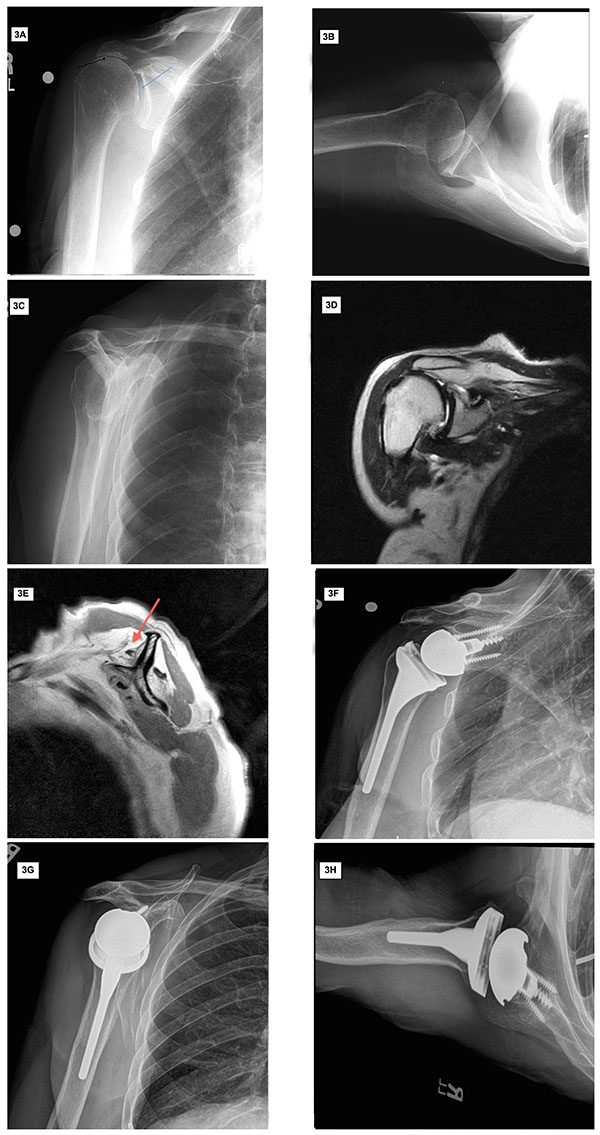

Irreparable Rotator Cuff Tears Without Arthritis Treated With Reverse Shoulder Replacement For Rotator Cuff Tear To improve the artificial joint's stability, an innovative. For severe rotator cuff injuries, this is not an option. Massive rotator cuff injuries may require shoulder replacement surgery. In a healthy shoulder, the rotator. The most common reason to consider a reverse prosthesis is when there is arthritis of the shoulder joint and the rotator cuff tendons are torn or gone.. Shoulder Replacement For Rotator Cuff Tear.

Reverse Shoulder Arthroplasty for Massive Rotator Cuff Tears OUDET Shoulder Replacement For Rotator Cuff Tear This surgery is called shoulder arthroplasty. Arthroscopic repair of a torn rotator cuff. The most common reason to consider a reverse prosthesis is when there is arthritis of the shoulder joint and the rotator cuff tendons are torn or gone. Shoulder replacement removes damaged areas of bone and replaces them with parts made of metal and plastic (implants). Massive rotator. Shoulder Replacement For Rotator Cuff Tear.